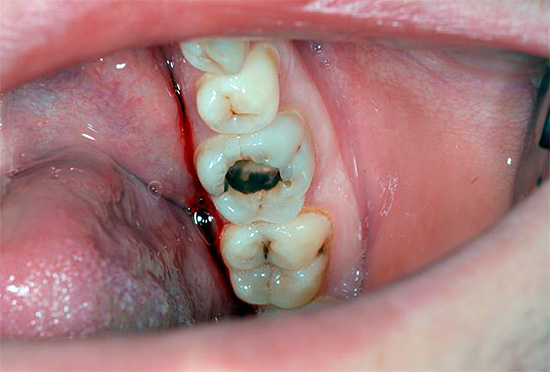

Tuttavia, il dolore severo può apparire solo quando la distruzione cariata raggiunge il confine smalto-dentina - in questo caso, i tessuti dei denti sono sensibili a varie sostanze irritanti (freddo, dolce, ecc.). In tali situazioni, per sbarazzarsi rapidamente delle sensazioni spiacevoli, è sufficiente eliminare semplicemente l'irritante e il dolore passerà immediatamente. Tuttavia, ovviamente, per un trattamento completo senza sigillo non sarà più sufficiente.

Il dolore nella carie media e profonda si verifica a causa del fatto che lo strato di dentina è penetrato da molti tubuli dentinali che alimentano il dente e ne determinano la sensibilità (e hanno anche una certa connessione con il "nervo" dentale). Quando lo strato di dentina viene distrutto, appare qualcosa come una "ferita" di dentina, che risponde all'azione degli stimoli.